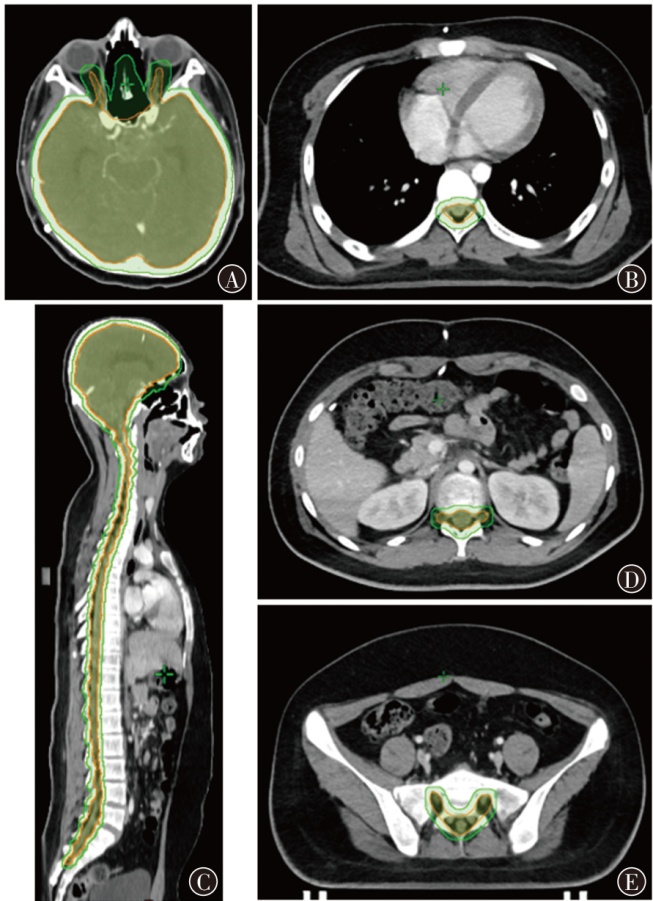

目的 探索质子调强放疗(IMPT)、光子固定野调强放疗(IMRT)以及光子螺旋断层放疗(TOMO)技术应用于儿童全中枢神经系统肿瘤照射的剂量学特点。方法 以1例山东省肿瘤防治研究院(山东省肿瘤医院)临床诊断为非典型畸胎样/横纹肌样瘤、脊膜转移、脑膜转移,行全脑全脊髓放疗(CSI)的14岁儿童患者靶区为例,根据靶区的临床处方和危及器官(OAR)的限值要求,分别设计IMPT、IMRT和TOMO计划。对各计划靶区的适形指数(CI)、均匀性指数(HI)和梯度指数(GI),以及正常组织的剂量体积指标进行评估,对比3类计划的剂量学特点。结果 IMPT计划的CI(0.71)、HI(0.05)和GI(3.13)均与IMRT计划(0.80、0.08、3.14)相当,TOMO计划的HI(0.03)、GI(2.54)较优,且均在临床接受范围内。IMPT计划中并行器官受照剂量低于IMRT和TOMO计划;IMPT计划中双肺V5为2.9%,IMRT为37.6%,TOMO为43.5%;IMPT计划的肝脏Dmean为0.01 Gy(RBE),IMRT计划为6.12 Gy,TOMO计划为6.39 Gy;IMPT计划中膀胱、直肠、股骨头均没有受量,而在IMRT和TOMO计划中均有低剂量辐射。对于毗邻靶区和包含在靶区内的串行器官,IMPT计划中脊髓和脑干的Dmax分别为39.89和39.88 Gy(RBE),IMRT计划分别为39.43 和38.59 Gy,TOMO计划分别为38.41和37.69 Gy。IMPT计划中低剂量区显著优于光子放疗计划,其中患者体内10%的处方剂量区域所占的绝对体积IMPT计划较IMRT计划减少了70.10%,较TOMO计划减少了76.96%;30%的处方剂量体积IMPT计划较IMRT计划减少了53.49%,较TOMO计划减少了62.51%;50%的处方剂量体积IMPT计划较IMRT计划减少了39.06%,较TOMO计划减少了42.23%。结论 在儿童CSI中,IMPT计划的低剂量区与并行OAR受照剂量显著少于IMRT和TOMO计划。3种计划的CI、HI和GI均能满足临床要求。对于毗邻靶区和包含在靶区内的串行器官,IMPT计划的Dmax可能比IMRT和TOMO计划剂量更高。

Objective To explore the dosimetric characteristics of intensity modulated proton therapy (IMPT),intensity modulated radiation therapy (IMRT) and tomotherapy (TOMO) techniques applied in the irradiation of pediatric whole central nervous system tumors. Methods Taking the target area of a 14-year-old pediatric patient clinically diagnosed with atypical teratoid/rhabdomyoid tumor,meningeal metastasis by Shandong Cancer Hospital and Institute,and undergoing craniospinal irradiation (CSI) as an example,IMPT,IMRT and TOMO plans were designed respectively based on the clinical prescription of the target area and the limit requirements of organs at risk (OARs). The conformal index (CI),homogeneity index (HI) and gradient index (GI) of each planning target volume,as well as the dose volume index of normal tissues,were evaluated to compare the dosimetric characteristics of the three types of plans. Results The CI (0.71),HI (0.05) and GI (3.13) of the IMPT plan were comparable to those of IMRT plan (0.80,0.08,3.14). The HI (0.03) and GI (2.54) of the TOMO plan were excellent,which were all within the clinically acceptable range. The irradiation dose to parallel organs in the IMPT plan was lower than that in the IMRT and TOMO plan. In the IMPT plan,V5 of lungs was 2.9%,IMRT plan was 37.6%,and TOMO plan was 43.5%. The Dmean of liver in the IMPT plan was 0.01 Gy(RBE),IMRT plan was 6.12 Gy,and TOMO plan was 6.39 Gy. In the IMPT plan,none of the bladder,rectum,and femoral head received the dose,while there was low-dose radiation in both IMRT and TOMO plan. For serial organs adjacent to and within the target area,the Dmax of spinal cord and brainstem in IMPT plan was 39.89 and 39.88 Gy(RBE),respectively; in IMRT plan,they were 39.43 and 38.59 Gy,respectively; and in TOMO plan,they were 38.41 and 37.69 Gy,respectively. The low-dose area in the IMPT plan was significantly better than the photon radiotherapy plans. Among them,the absolute volume IMPT plan occupied by 10% of the prescribed dose area in the patient's body was reduced by 70.10% compared with IMRT plan and 76.96% compared with TOMO plan; the 30% prescribed dose volume IMPT plan was reduced by 53.49% compared with IMRT plan and 62.51% compared with TOMO plan; the 50% prescribed dose volume IMPT plan was reduced by 39.06% compared with IMRT plan and 42.23% compared with TOMO plan. Conclusions The IMPT plan demonstrated significantly reduced low-dose exposure and lower doses to parallel OARs compared to both IMRT and TOMO plans in pediatric CSI. The CI,HI and GI of the three plans can all meet the clinical requirements. However,for serial organs adjacent to and within the target area,the Dmax of the IMPT plan may be higher than that of IMRT and TOMO plans.